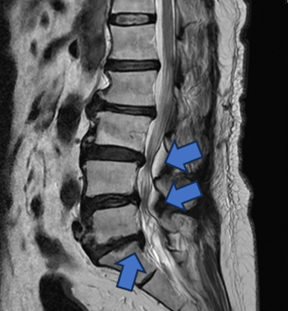

圖三、【手術前】有脊椎滑脫不穩定及脊椎狹窄造成神經壓迫的情況。

圖五、手術以間接減壓的方式,從後腹腔進入(紅色箭頭),有別傳統從脊椎腔(藍色箭頭)切入,因此能夠不破壞骨骼不撥弄脊椎神經,大幅減低神經損傷機率。